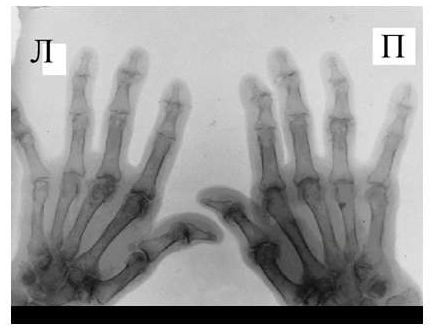

Также хотелось обратить внимание на неправильно выбираемую зону обследования. Например, зачастую при наличии односторонних клинических изменений в одном пястно-фаланговом или плюсне-фаланговом суставе врачи ограничиваются рентгенографией исключительно этой области. Однако, именно характер патологических изменений в обеих кистях, их локализация и распространённость, анализ того какие группы суставов изменяются в самом начале заболевания должны обязательно учитываться при оценке рентгенограмм для того, чтобы правильно интерпретировать полученные данные и провести дифференциальный диагноз между различными ревматическими заболеваниями. Поэтому в ревматологической практике для уточнения диагноза необходимо проводить по показаниям либо прямую сравнительную рентгенограмму кистей с захватом лучезапястных суставов либо прямую сравнительную рентгенограмму стоп.

Исходя из нашего опыта, результаты рентгенографии нередко могут зависеть от техники и правильного позиционирования объекта съемки. В настоящее время требованием всех протоколов исследований является соблюдение максимально унифицированных условий проведения рентгенограмм кистей и стоп. Так для общей оценки поражения суставов необходимо снимать обе кисти или стопы на одной пленке, обязателен захват лучезапястного сустава. Требования к расположению пациента при рентгенографии кистей и стоп изложены в соответствующих руководствах по рентгенологии. Врачу общей практики при направлении к рентгенологу обязательно необходимо указывать, что больной направляется на сравнительную рентгенограмму кистей в прямой проекции с захватом лучезапястных суставов или на прямую сравнительную рентгенограмму стоп.

Одним из главных отличительных признаков ревматоидного артрита (РА) от других заболеваний является симметричность изменений мелких суставах кистей и стоп, которые становятся суставами-«мишенями» в первую очередь и поэтому именно эти области изучаются для определения стадии заболевания. Наиболее часто используемой в повседневной практике рентгенологической классификацией является деление ревматоидного артрита на стадии по Steinbrocker в различных модификациях.

Основные симптомы

Основными рентгенологическими симптомами РА являются следующие: остеопороз, кистовидные просветления костной ткани (кисты), сужение суставной щели, эрозии суставов, костные анкилозы, деформации костей, остеолиз, вывихи, подвывихи и сгибательные контрактуры суставов. Рентгенологическая диагностика развернутых стадий РА, исходя из нашей практики, как правило, затруднений не вызывают.

Рис. 4. Изменения кистей при ревматоидном артрите (а остеопороз, бсужение суставных щелей, в кистовидные просветвления, г костные эрозии, д анкилозирование)

Необходимо также помнить, что, как правило, при РА эрозии не предшествуют околосуставному остеопорозу, кистам и сужению суставных щелей. Имеет место последовательность развития стадий РА (см. рис. 4), в отличие от эрозивных артритов другого генеза (псориатического, серонегативного)